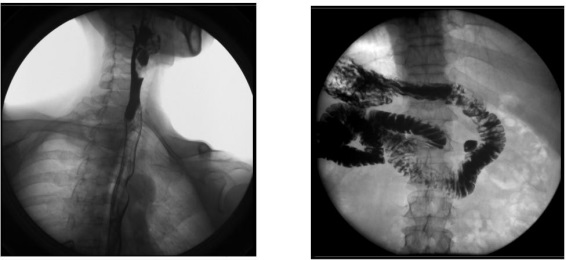

平板數(shù)字胃腸機(jī)臨床影像

3、其他造影:適用于各種普通及特殊造影,如口服膽囊造影、靜脈膽道造影、T 管造影、逆行胰膽管造影(ERCP)、靜脈腎盂造影(IVP)、子宮輸卵管造影等。

1) 婦科:可檢查輸卵管堵塞、輸卵管粘連、輸卵管積水等慢性輸卵管疾病導(dǎo)致的不孕,可明確顯示輸卵管堵塞的部位、程度及性質(zhì),還可辨認(rèn)子宮內(nèi)膜情況,輸卵管和盆腔的結(jié)核病變情況;

2) 肝膽外科:膽管手術(shù)后,切開膽總管植入 T 管引流,起支撐作用,防止術(shù)后膽總管狹窄,術(shù)后應(yīng)用胃腸機(jī)進(jìn)行膽管造影(T 管造影),檢查膽道內(nèi)有無殘留結(jié)石及異物,是否通暢無阻, 對手術(shù)進(jìn)行評估;